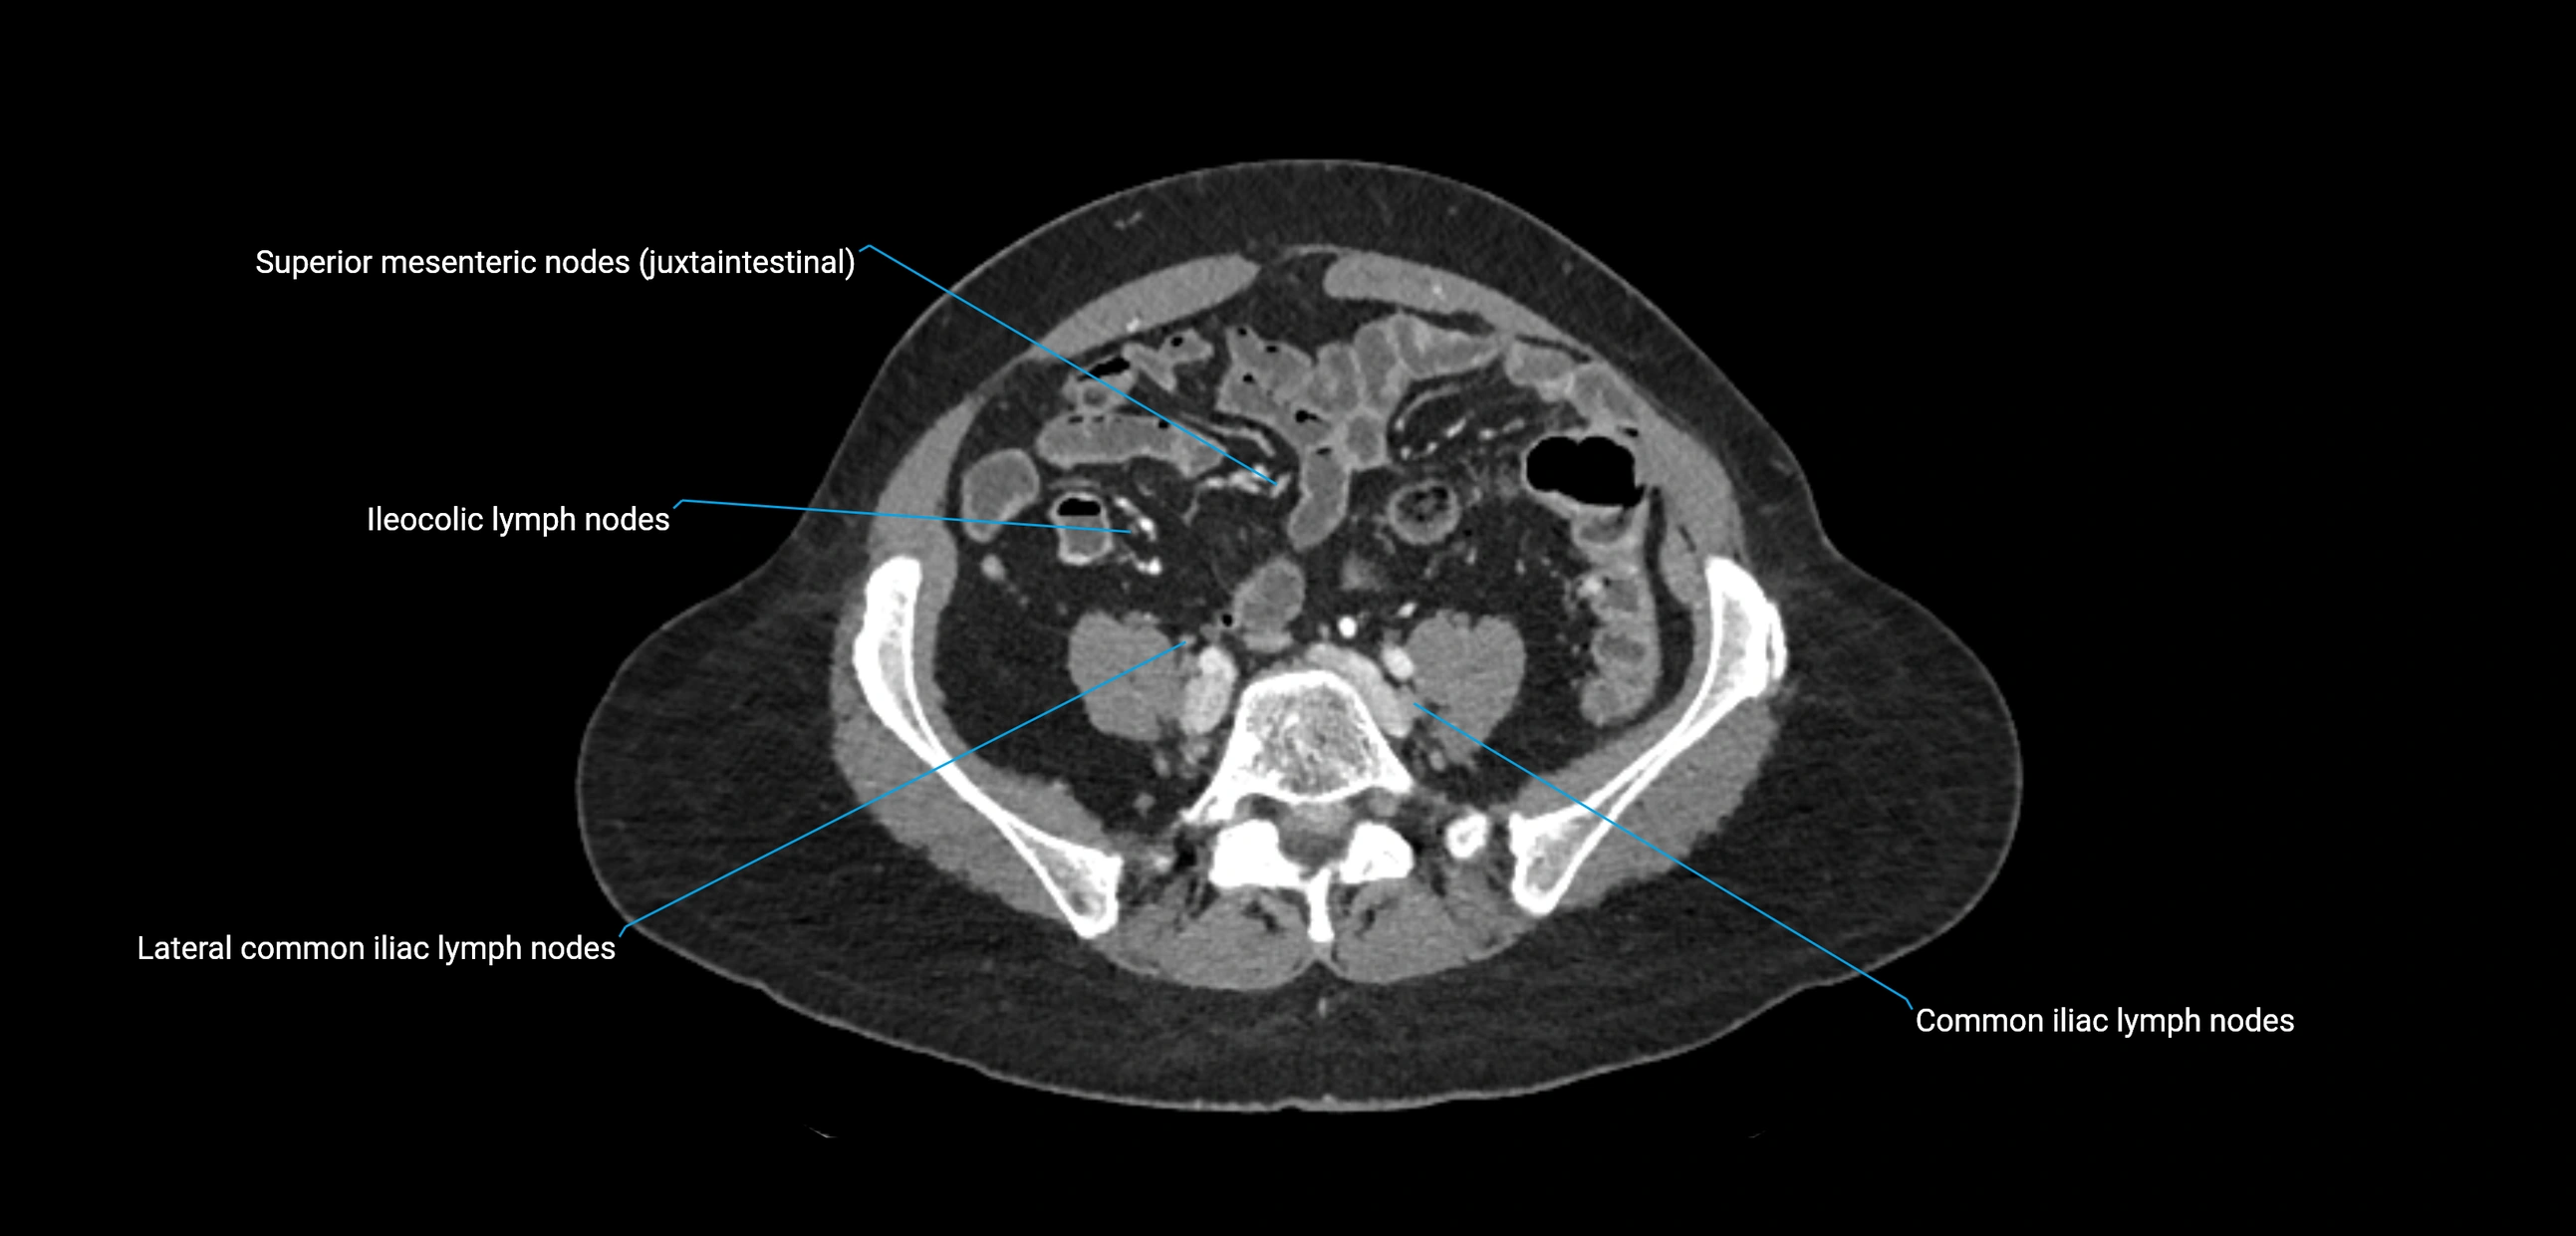

The lateral aortic lymph nodes (also called para-aortic lymph nodes) are a major group of retroperitoneal lymph nodes located along the abdominal aorta and its branches. They lie between the diaphragmatic crura superiorly and the bifurcation of the aorta at L4 inferiorly.

They are positioned on both sides of the abdominal aorta:

These nodes receive lymph from a wide range of abdominal and pelvic structures. Specifically, they drain lymph from the kidneys, suprarenal glands, gonads (testes/ovaries), uterus, uterine tubes, and pelvic organs, before converging into the lumbar lymphatic trunks, which terminate in the cisterna chyli → thoracic duct.

Clinically, the lateral aortic lymph nodes are critically important in oncology, being involved in the spread of testicular cancer, ovarian cancer, endometrial cancer, cervical cancer, renal malignancies, and retroperitoneal lymphomas. They are also key targets in retroperitoneal lymph node dissection (RPLND) for testicular tumors.

CT Appearance

CT Pre-Contrast:

• Nodes appear as soft-tissue density nodules adjacent to the aorta and IVC

CT Post-Contrast:

• Normal nodes enhance homogeneously

• Malignant nodes may show heterogeneous enhancement, central necrosis, or conglomerate formation

• Size >1 cm short axis is suspicious, though morphology and distribution are equally important